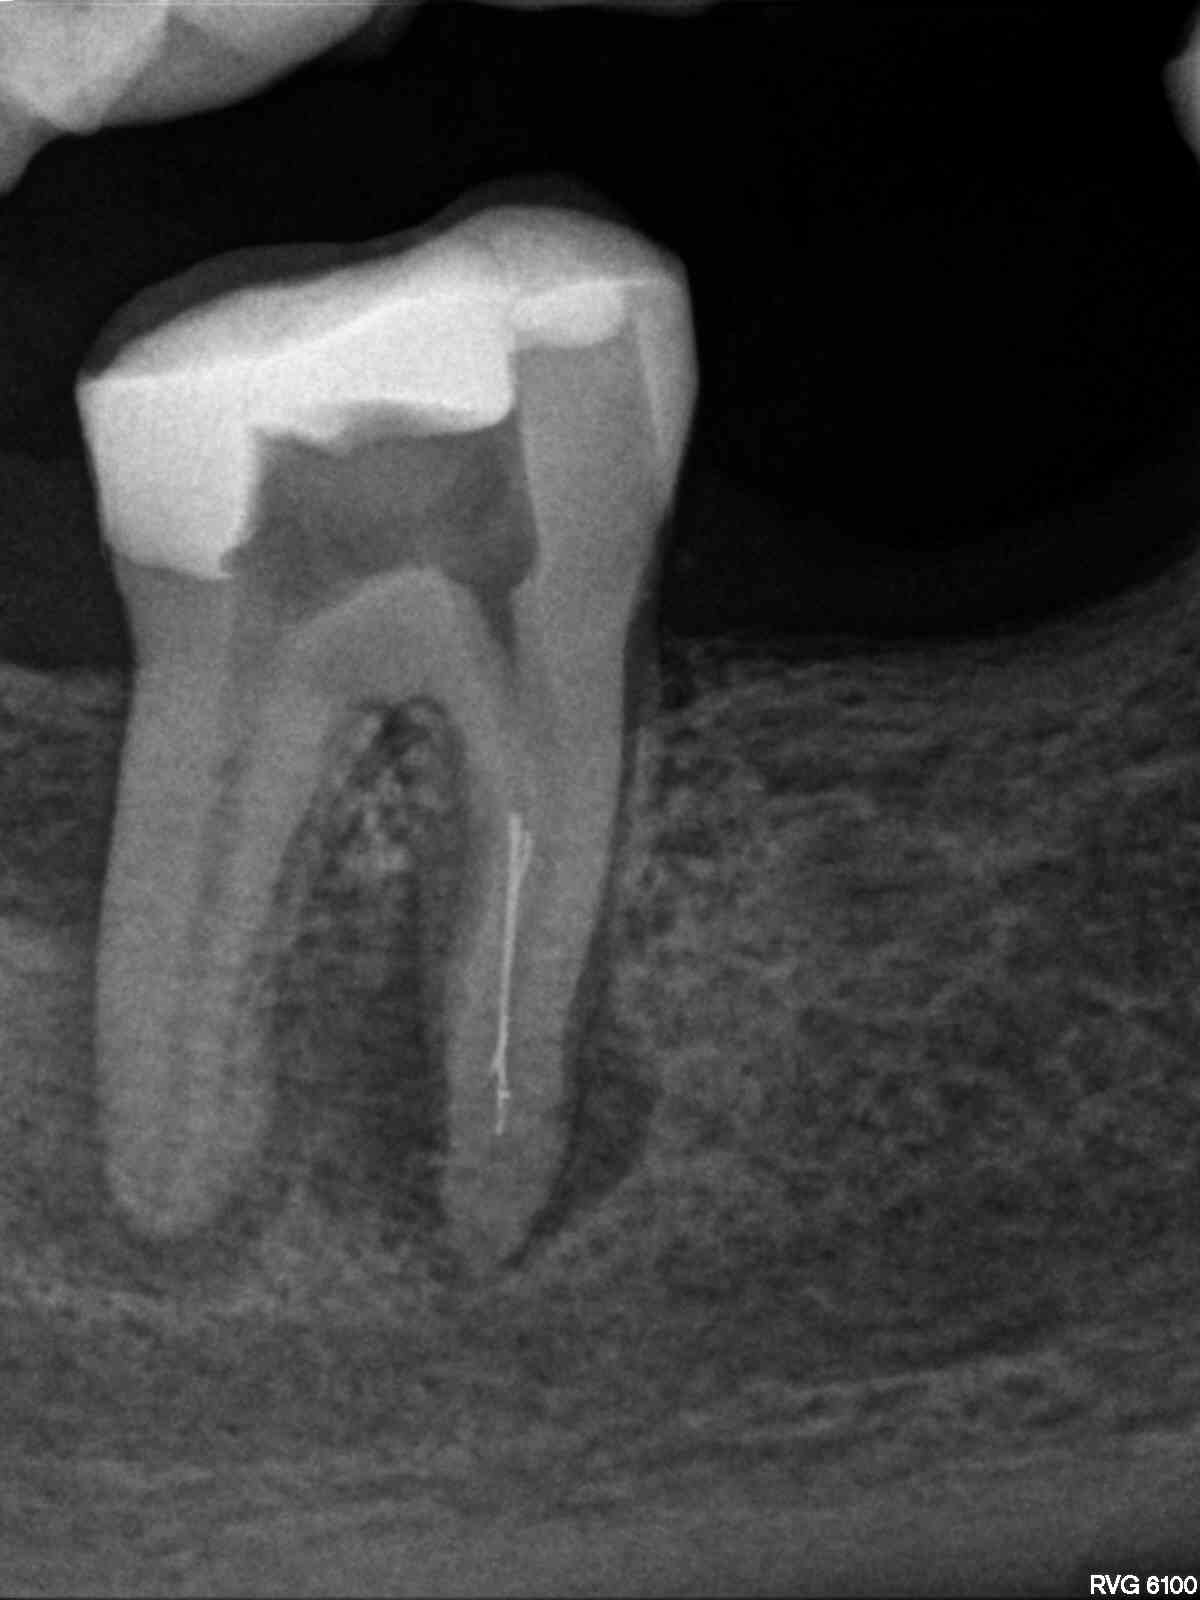

R1

1200 × 1600

Fragmententfernung